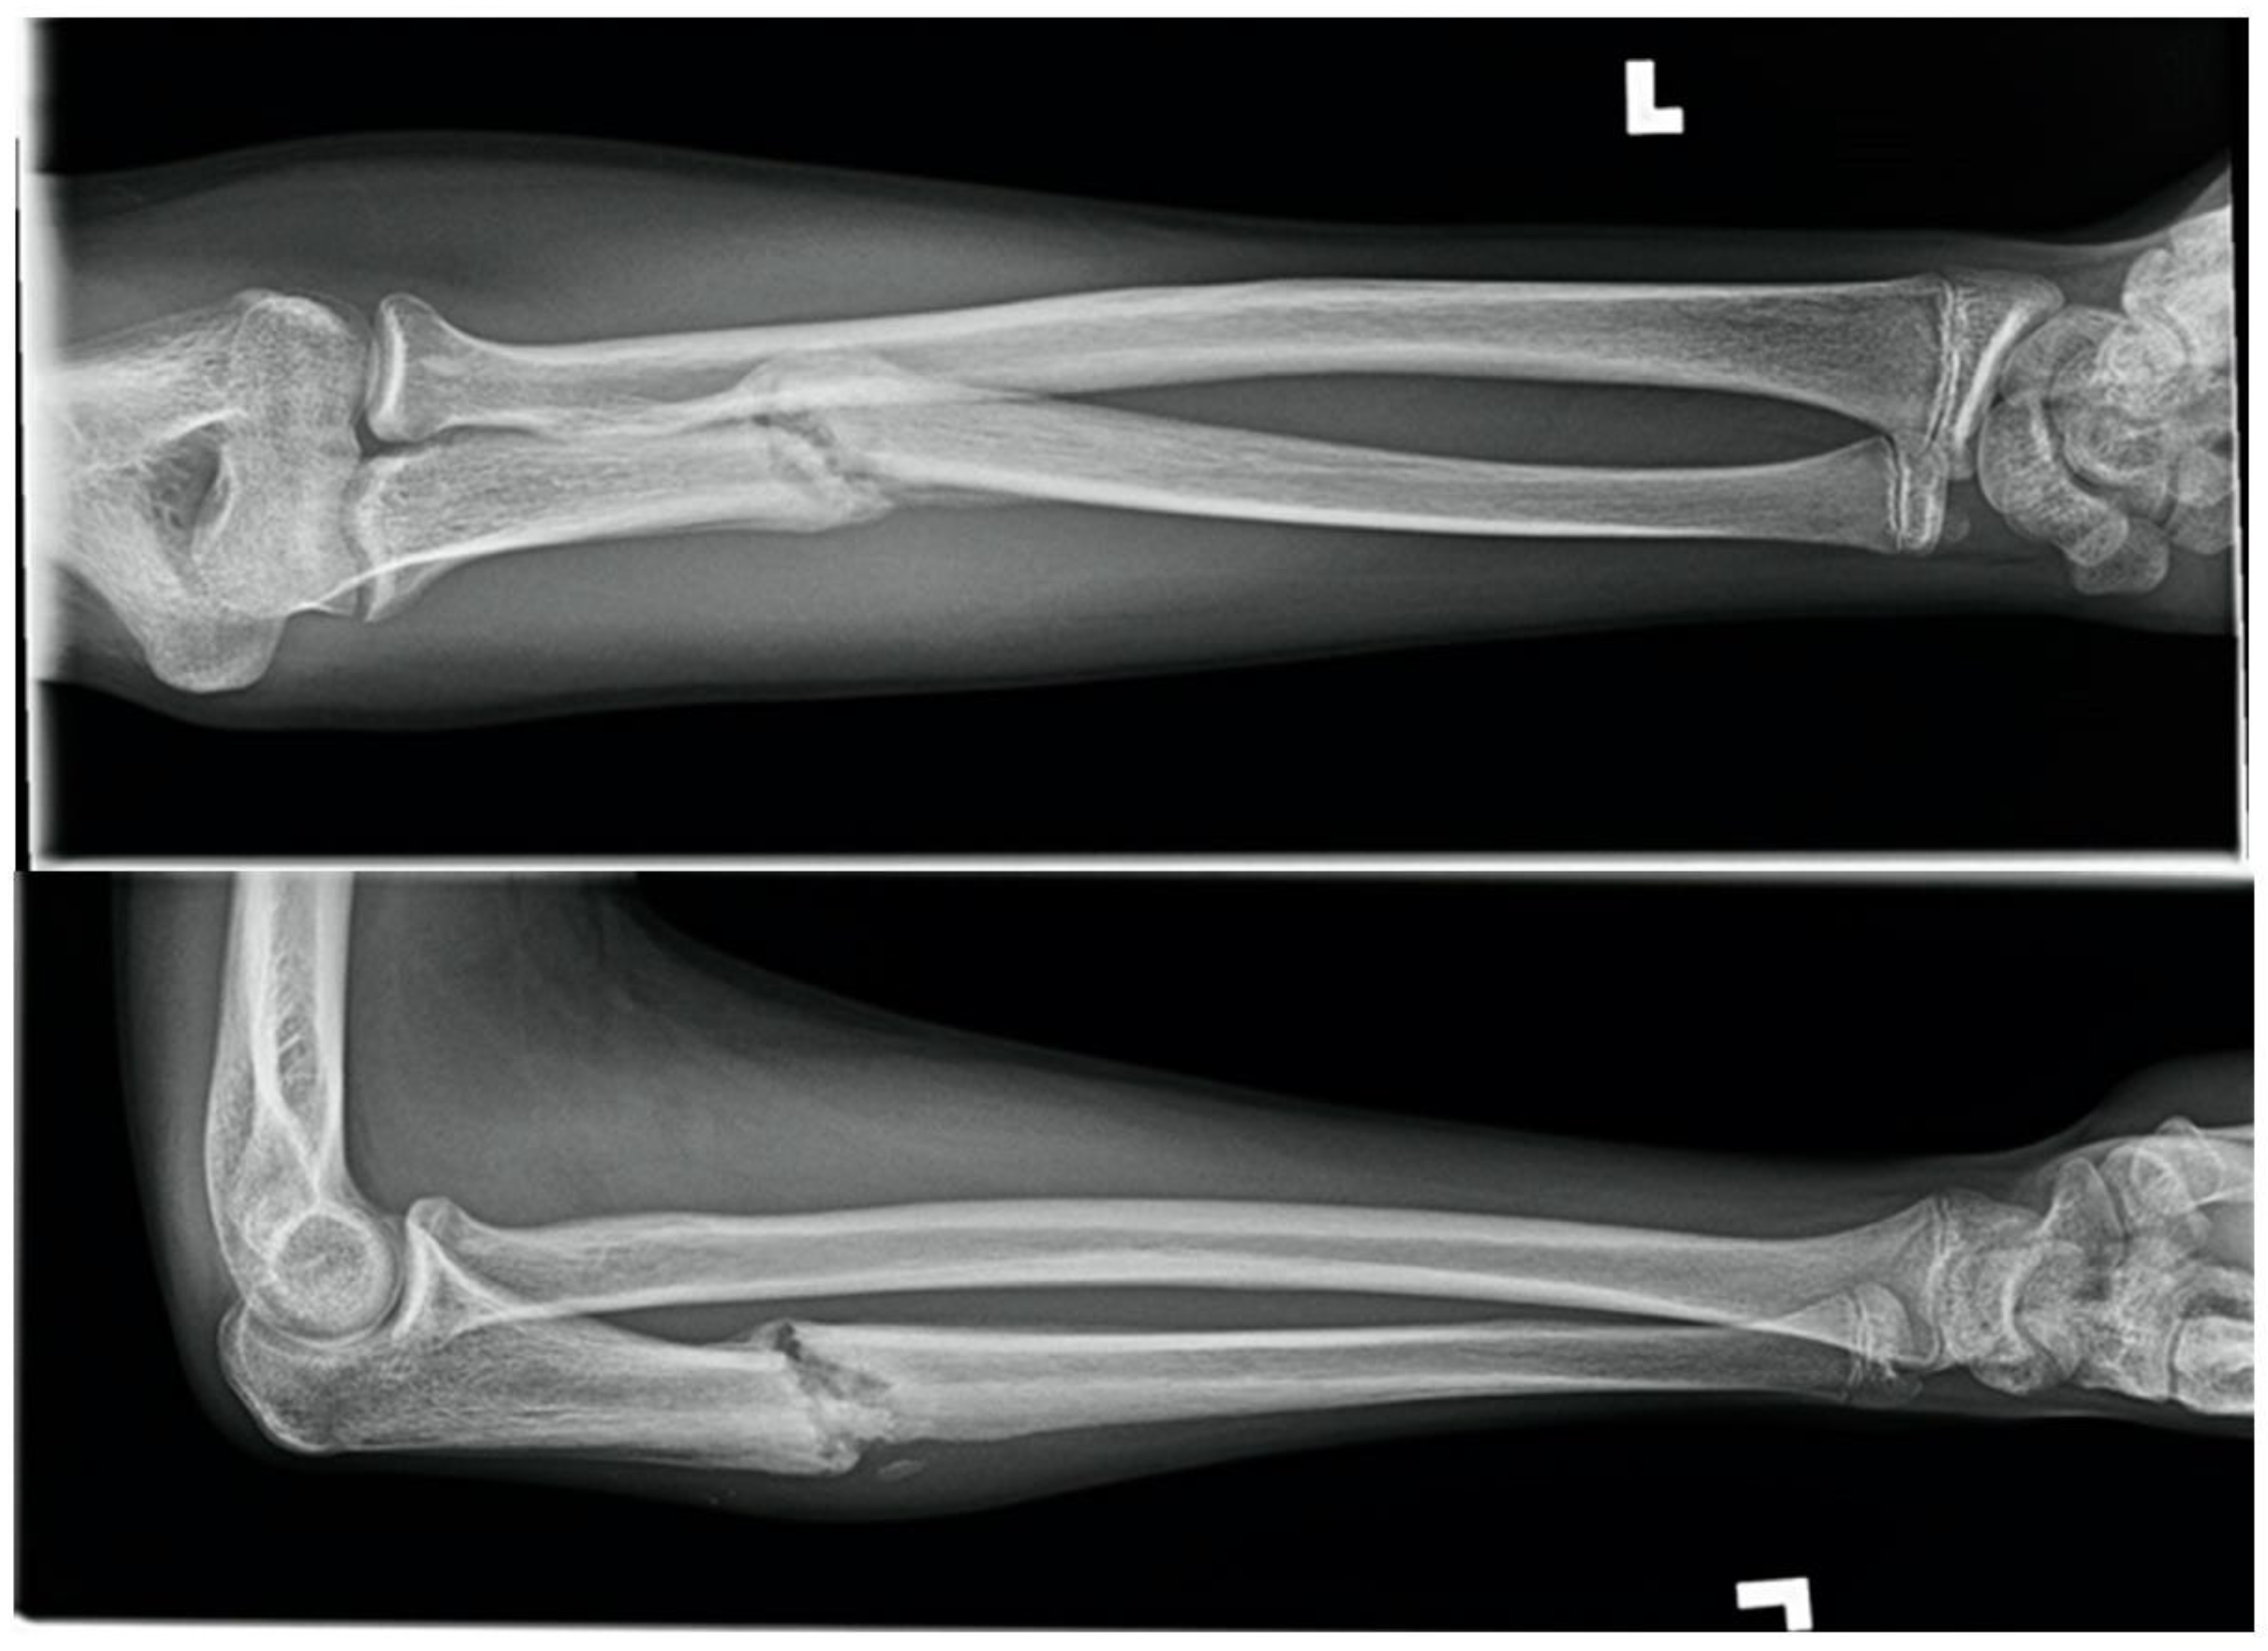

1.2. Monteggia Fracture-Dislocation on a Motorcycle, Fifteen Weeks in a 14-Year-Old Male

A fourteen-year-old male presented with a closed, neurovascularly intact, displaced, and moderately comminuted diaphyseal ulnar fracture with associated posterolateral dislocation of the radial head, also known as a Monteggia fracture-dislocation. The injury occurred after ejection from an off-road motorcycle at moderate speed. There was an associated unstable C5/6 cervical spine fracture-dislocation and disc rupture with no neurological symptoms. There was no known medical history. The forearm fracture-dislocation was reduced and splinted in the trauma bay by pediatric orthopedics with near-anatomic alignment. Neurosurgery colleagues managed the spine injury with emergent anterior discectomy and fusion without complication from which he recovered well with no neurologic sequelae. There was no history of cigarette smoking, but the patient was a current user of e-cigarettes.

At one-week post-injury radiographs demonstrated good alignment of the fracture and radio-capitellar joint. A long-arm circumferential cast was placed. At three weeks post-injury radiographs again demonstrated acceptable alignment and casting was continued. At seven weeks post-injury, there was no radiographic evidence of healing, and a removable cast was prescribed with instructions for twice daily non-weightbearing range of motion exercises. The patient was counselled to discontinue EC use. At eleven weeks post-injury there was continued pain at the fracture site with no radiographic evidence of healing (Figure 2). Delayed union was diagnosed as the expected healing time of a closed pediatric forearm fracture is approximately 5.5 weeks [1]. Fifteen weeks post-injury the patient had symptomatic improvement with resolution of fracture-site tenderness and radiographs showed evidence of bony union.

Figure 2.

Eleven-week forearm radiographs demonstrating no union after Monteggia fracture-dislocation in a pediatric EC user.